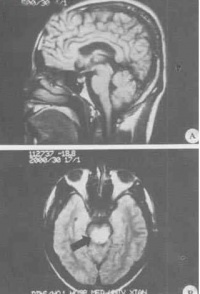

言语不清,嗜睡2天,于2005年11月24日急诊入院。2005年11月20日上午,患者在广州某镇探亲时家务劳动后,上楼时出现行走无力,下午自觉视物模糊,不伴发热、恶寒、头痛、头晕、咳嗽、咽痛、恶心、呕吐等症状。11月21日上午患者步行到广州市某镇医院按“上呼吸道感染”治疗无效。11月22日下午患者出现行走无力加重,需人搀扶,并出现言语欠清晰、精神差,被家人于当晚送回湖南当地县人民医院诊治。查体:嗜睡,反应迟钝,言语欠清晰,口角向左歪,伸舌右偏,右上下肢肌力IV级,左上下肢肌力正常,病理反射(—)。头颅CT平扫未见异常。按“脑梗塞”治疗病情无好转,故于11月24日下午转至我院神经内科重症监护病房按重症脑梗塞诊治。入院时查体:T36.7℃P86次/分R20次/分BP105/71mmHg嗜睡,言语欠清晰,右眼睑稍下垂,右眼内收及左眼外展受限,右侧鼻唇沟稍变浅,伸舌右偏,双侧咽反射减弱,心、肺、腹均未见异常,左上、下肢肌力IV级加,右上、下肢肌力III级加,四肢肌张力稍低,腱反射减退,指鼻及轮替试验及感觉功能检查无法配合。颈软,克、布氏征(—),右巴氏征(+),左巴氏征(—)。实验室检查:血常规:WBC总数:10.4×109/L,分类正常;电解质、肝、肾功能血脂血糖血气分析均正常。11月25日上午患者出现昏睡,完全性失语,四肢肌力明显减退,右上肢肌力0级,左上、下肢及右下肢肌力均II级。查头颅MRI示:中脑与桥脑交界处见片状稍长T1稍长T2信号,边界欠清晰,中脑导水管及第四脑室未见明显受压;头颅MRI增强:脑干异常信号,未见明显强化,考虑脑干梗塞。11月26日患者陷入浅昏迷,腰穿查脑脊液压力95mmH2O,外观无色,清亮,潘氏实验(+),总蛋白定量0.58g/L,白细胞数76×106/L,单个核细胞90%,多个核细胞10%,葡萄糖2.59mmol/L,氯化物117mmol/L,故诊断为脑干脑炎,给予地塞米松10mg静滴,每日一次,同时予抗病毒,抗感染等治疗,12月2日患者意识转清醒,但言语模糊不清,右上肢肌力II级,右下肢肌力0级,左上下肢肌力II-III级。14天后停地塞米松改为口服强的松30mg/天,逐渐减量,患者入院第20天因经济困难出院,出院时查体:右眼内收及左眼外展受限,伸舌稍右偏,双上肢肌力III-IV,双下肢肌

脑干脑炎

力III级,病理征阴性,复查脑脊液:压力180mmH2O,无色,清亮,潘氏实验(—),脑脊液蛋白定量0.23g/L,白细胞数16个/L,单核细胞为主,葡萄糖3.4mmol/L,氯化物128mmol/L。2006年1月17日复诊:患者仍行走不稳,需人搀扶。查:神清语利,计忆力、定向力、记算力正常,双眼球运动正常,双鼻唇沟对称,伸舌稍右偏,四肢肌力肌张力正常,双巴氏征阳性,深浅感觉检查正常。双侧指鼻试验稍差,Romberg征睁眼(+),闭眼(+)。脑电图正常;视觉、脑干听觉诱发电位检查:右眼VEP潜伏期延长,波幅在正常范围内;左眼VEP潜伏期、波幅在正常范围内;右耳BAEP波形分化不良,左耳BAEPⅠ、Ⅲ、Ⅴ波幅,潜伏期正常;四肢肌电图检查:左腓总神经运动传导波幅降低。2006年3月15日随访,患者行走正常,完全康复。查体无异常。

讨论:脑干脑炎临床表现多种多样,但缺乏典型的症状和体征,容易误诊。本病例患者以突发肢体瘫痪起病,发病前无感染史及病程中无发热史,头颅CT平扫未见异常,头颅

MRI增强:脑干异常信号,未见明显强化,考虑脑干梗塞。故临床误诊为重症脑梗塞。误诊原因可能为:(1)近年来青壮年脑梗塞发病率增高;(2)临床医生对突发肢体瘫痪和意识障碍患者,过分依赖头颅CT和MRI等影像学诊断结果;(2)发病前无感染史及发病前后病程中无发热史导致忽视了炎性疾病的可能。文献报道脑干脑炎的发病特点为:1.任何年龄都可发病,以青壮年居多。2.大多患者发病前1—4周有上呼吸道感染或其他病毒感染史。3.起病急骤,往往早期出现精神症状和意识障碍,通常在较短时间内出现双侧脑神经麻痹,伴有一侧或双侧的肢体运动障碍感觉障碍,但长束征少见,症状和体征较弥散很少局限于某一部位,4.脑脊液基本正常,蛋白轻度增高,细胞以淋巴细胞和单核细胞为主。5.病程常有自限性,经7—8周治疗后大部分好转或痊愈。6.激素早期治疗有效,预后好。7.头颅CT和MRI的异常率低。本例开始按脑梗塞治疗效果不佳,发现脑脊液异常后,按脑干脑炎以地塞米松等治疗,患者完全康复。我们推测该病发病机制可能是病毒的直接侵润损伤或病毒感染后的免疫损伤。MasaakiOdaka等研究认为许多Bickerstaff脑干脑炎患者都合并有Guillain-Barre综合征轴突改变,暗示这两种病是相近的,二者属于同一疾病谱。